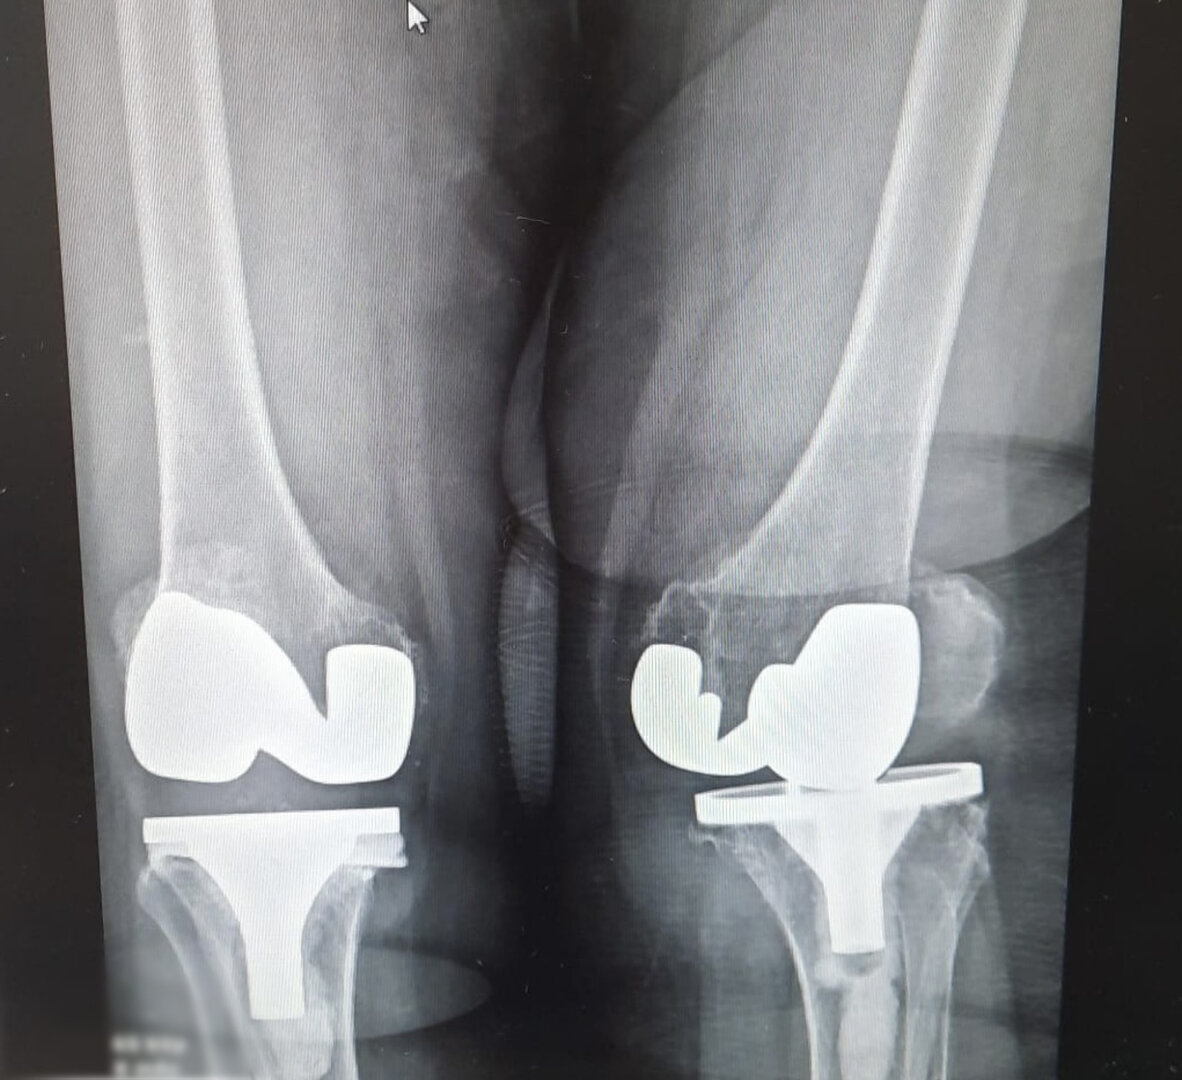

Aşınmış, hasar görmüş ya da eklem yüzeyleri tamamen bozulmuş diz ekleminin, yapay bir eklemle değiştirme işlemidir. Ameliyatta, ağrıya neden olan hasarlı kemik ve kıkırdak dokular çıkarılarak; yerine metal ve özel plastikten yapılmış, uzun ömürlü bir protez yerleştirilir. Bu sayede diz, tekrar ağrısız ve stabil bir şekilde çalışır hale gelir.

Eklem yüzeyleri özel kılavuzlar yardımı ile temizlendikten sonra metal protez eklem yüzeylerine bir kemik çimentosu ile adapte diyoruz. Bu iki metal yüzeyin sürtünmesini azaltmak için polietilenden yapılmış özel bir plastik tabakayı sisteme dahil ediyoruz.